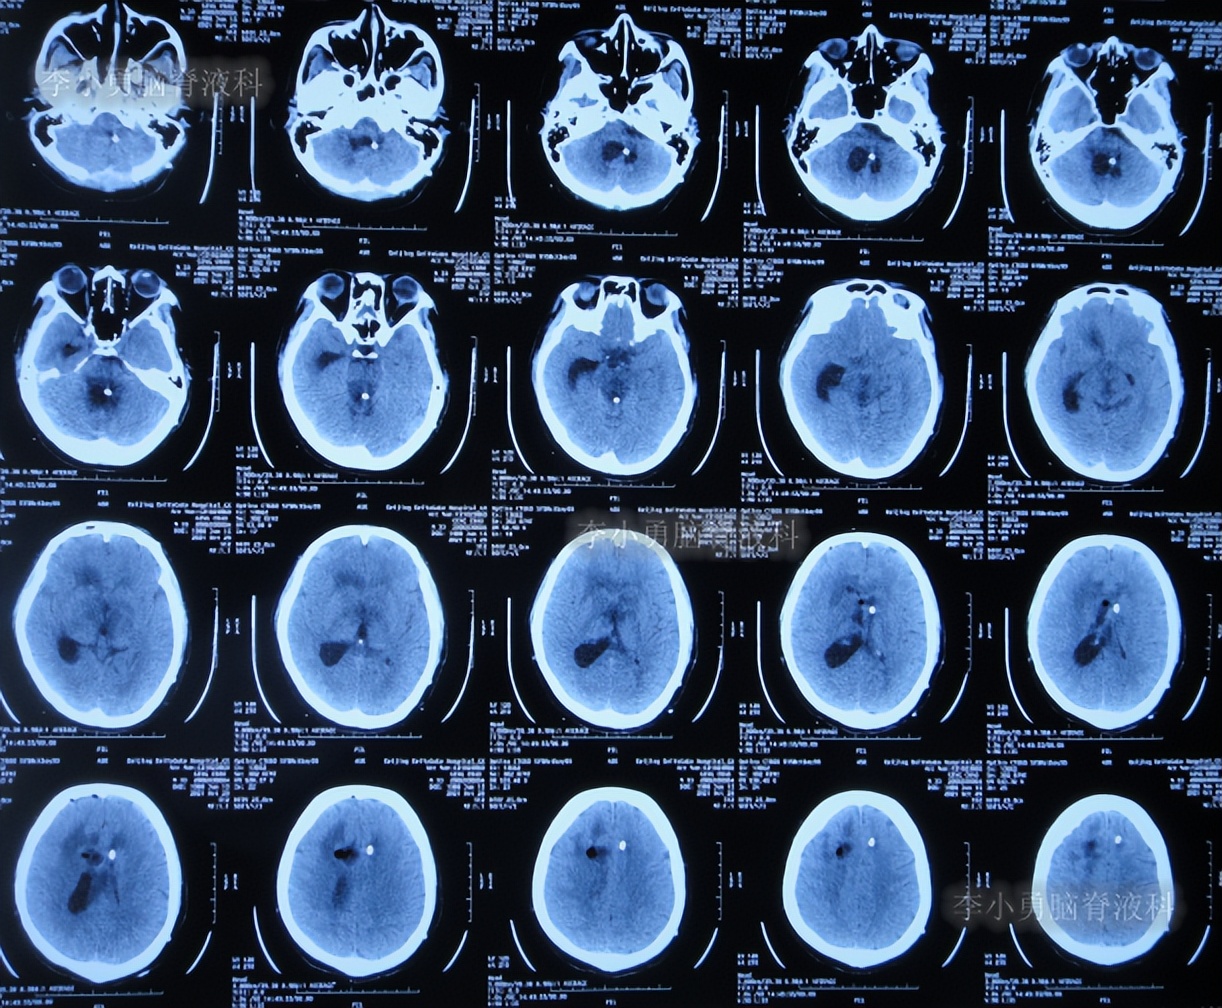

二、第1次在李小勇脑脊液科治疗过程和结果

2020年6月4日(脑囊虫切除术+第三脑室造瘘术后2年5个月,2次脑室腹腔分流术均堵管,期间历经5次住院但脑积水仍反复复发)住入李小勇脑脊液科,入院时:神志朦胧,饮食差,问答有误,自己站立不稳,双眼对视(图-19);既往史:口服抗癫痫药物,青霉素过敏。头颅CT示鞍上占位术后,脑室内可见引流管,脑室系统扩张(图-20)。

图-20:2020年6月4日头颅CT